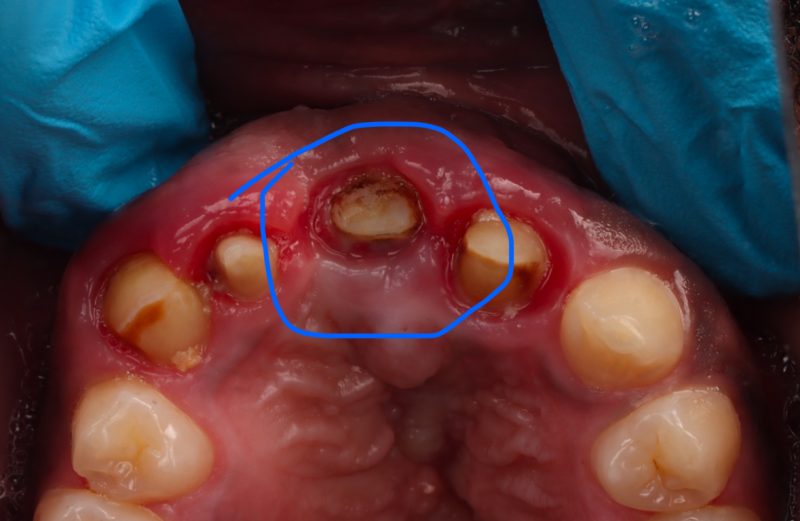

Patient had biomet 3I implant placed elsewhere. Had a cement retained crown #10. Its now completely covered by soft tissue. Any tips for removal of the screw?